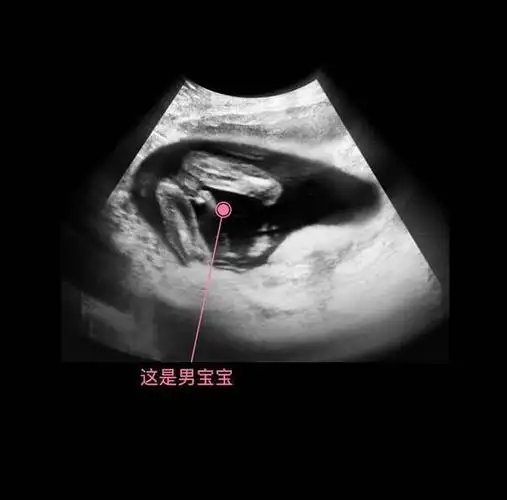

孕11周:生殖器发育(男)怀孕第11周胎儿身长约40毫米,体重约10克,形状

广州妈妈告诉你两张b超图片便可提前知道是男是女